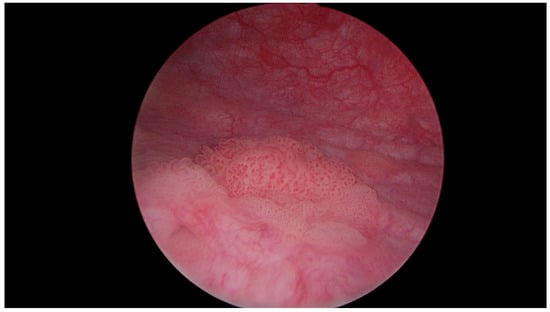

Figure 5.

Multiple papillary urothelial carcinoma of the urinary bladder—in the lower part of the image, at 8 o’clock, the vesical orifice of the right ureter is visible. Own study based on Ethical Approval of the University of Rzeszow, No. 29/05/2019. Titled 12. 2019, Evaluation of the efficacy of the in vitro photodynamic method in superficial bladder cancer, by M.D. Dominik Godlewski.